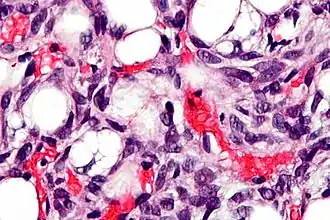

Lipoblast

Een lipoblast, ook wel steatoblast genoemd, is een precursorcel voor een adipocyt.[1] Alternatieve termen zijn onder meer adipoblast[2] en preadipocyt.[3] Vroege stadia zijn bijna niet te onderscheiden van fibroblasten.[4]

Liposarcomen ontstaan uit de lipoblasten of adipocyten in vetweefsel.